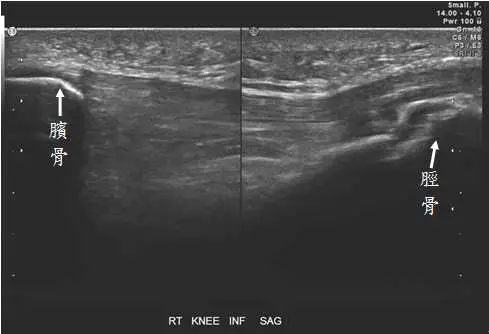

11 歲男童,主訴右膝疼痛,膝蓋前側之灰階及彩色杜卜勒超音波檢查如圖,最可能的診斷為何?

圖一(灰階超音波): 影像標示為「RT KNEE INF SAG」(右膝下方矢狀切面),可見左側標示為「髕骨」的高回聲骨性結構,右側標示為「脛骨」,兩者之間可見髕韌帶(patellar tendon)走行於皮下組織深面。髕韌帶遠端於脛骨粗隆附著處可見局部增厚,骨表面回聲不規則,有輕度軟組織腫脹,符合骨突炎(apophysitis)的灰階特徵。